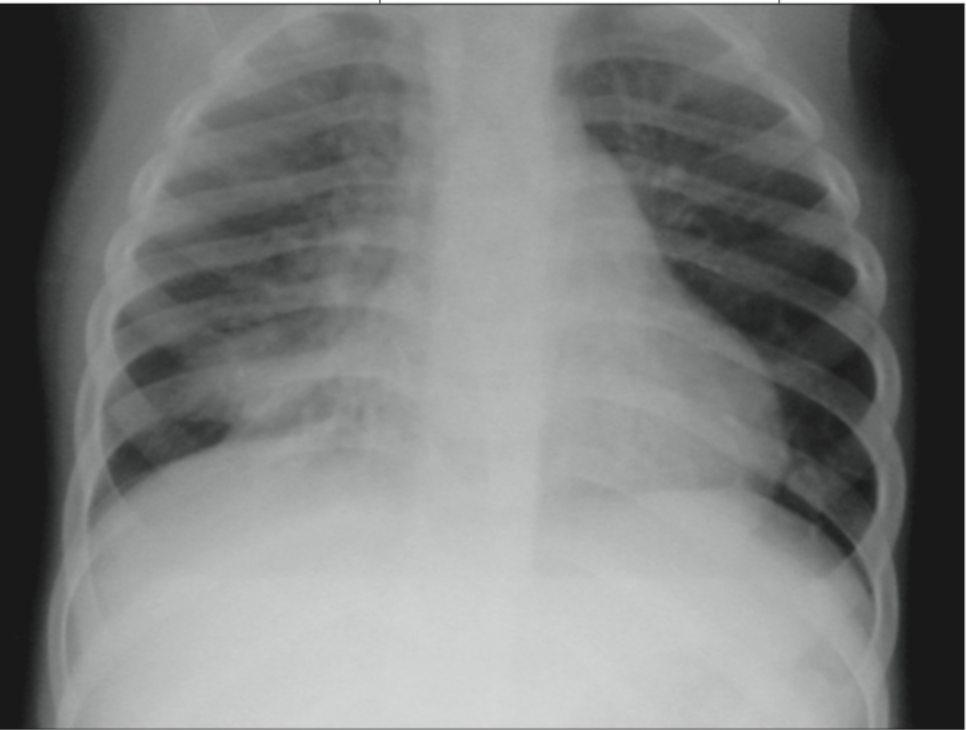

- 흉부 X-ray: 폐렴이나 흉막염 같은 폐 관련 질환을 확인하는 데 유용합니다.

흉부 X-ray에서 기관지 염증이 확인되었으며, 항생제와 기관지 확장제를 처방받아 증상이 완화되었습니다.